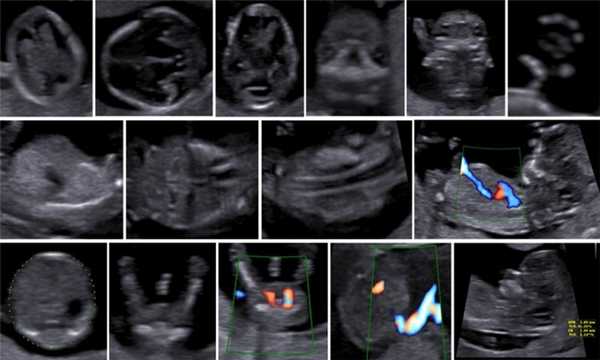

Описанные в литературе величины частоты выявления дефектов в I триместре беременности значительно различаются в зависимости от изученных популяций, методов и периодов [5]. По мере развития методов ультразвуковой диагностики усовершенствовался и анатомический анализ для I триместра беременности. Международное общество по применению УЗИ в акушерстве и гинекологии (International Society of Ultrasound in Obs tetrics and Gynecology - ISUOG) в 2013 г. предложило руководство для клинической практики, предполагающее проведение оценки анатомии плода между 11 нед 0 дней и 13 нед 6 дней беременности (рис. 3) [6].

В 90% случаев крупные анеуплоидии у плодов можно обнаружить с помощью комбинированной оценки возраста матери, измерений ТВП и сывороточных маркеров у матери (РАРР-А и свободный бета-ХГЧ) [8]. Результат такого скрининга можно улучшить, исследуя сывороточные маркеры раньше, на сроках от 9 до 10 нед, и проводя УЗИ на 12-й неделе для выявления дополнительных маркеров, таких как носовая кость плода, кровоток в венозном протоке и через трехстворчатый клапан (рис. 5) [9]. Кроме того, выявлять часто встречающиеся хромосомные аномалии у плода позволяет неинвазивное пренатальное тестирование (Non Invasive Prenatal Testing - NIPT).

Рис. 5. Оценка анеуплоидии по ультразвуковым маркерам: толщина воротникового пространства (a), носовая кость (b), венозный проток (c), кровоток через трехстворчатый клапан (d).